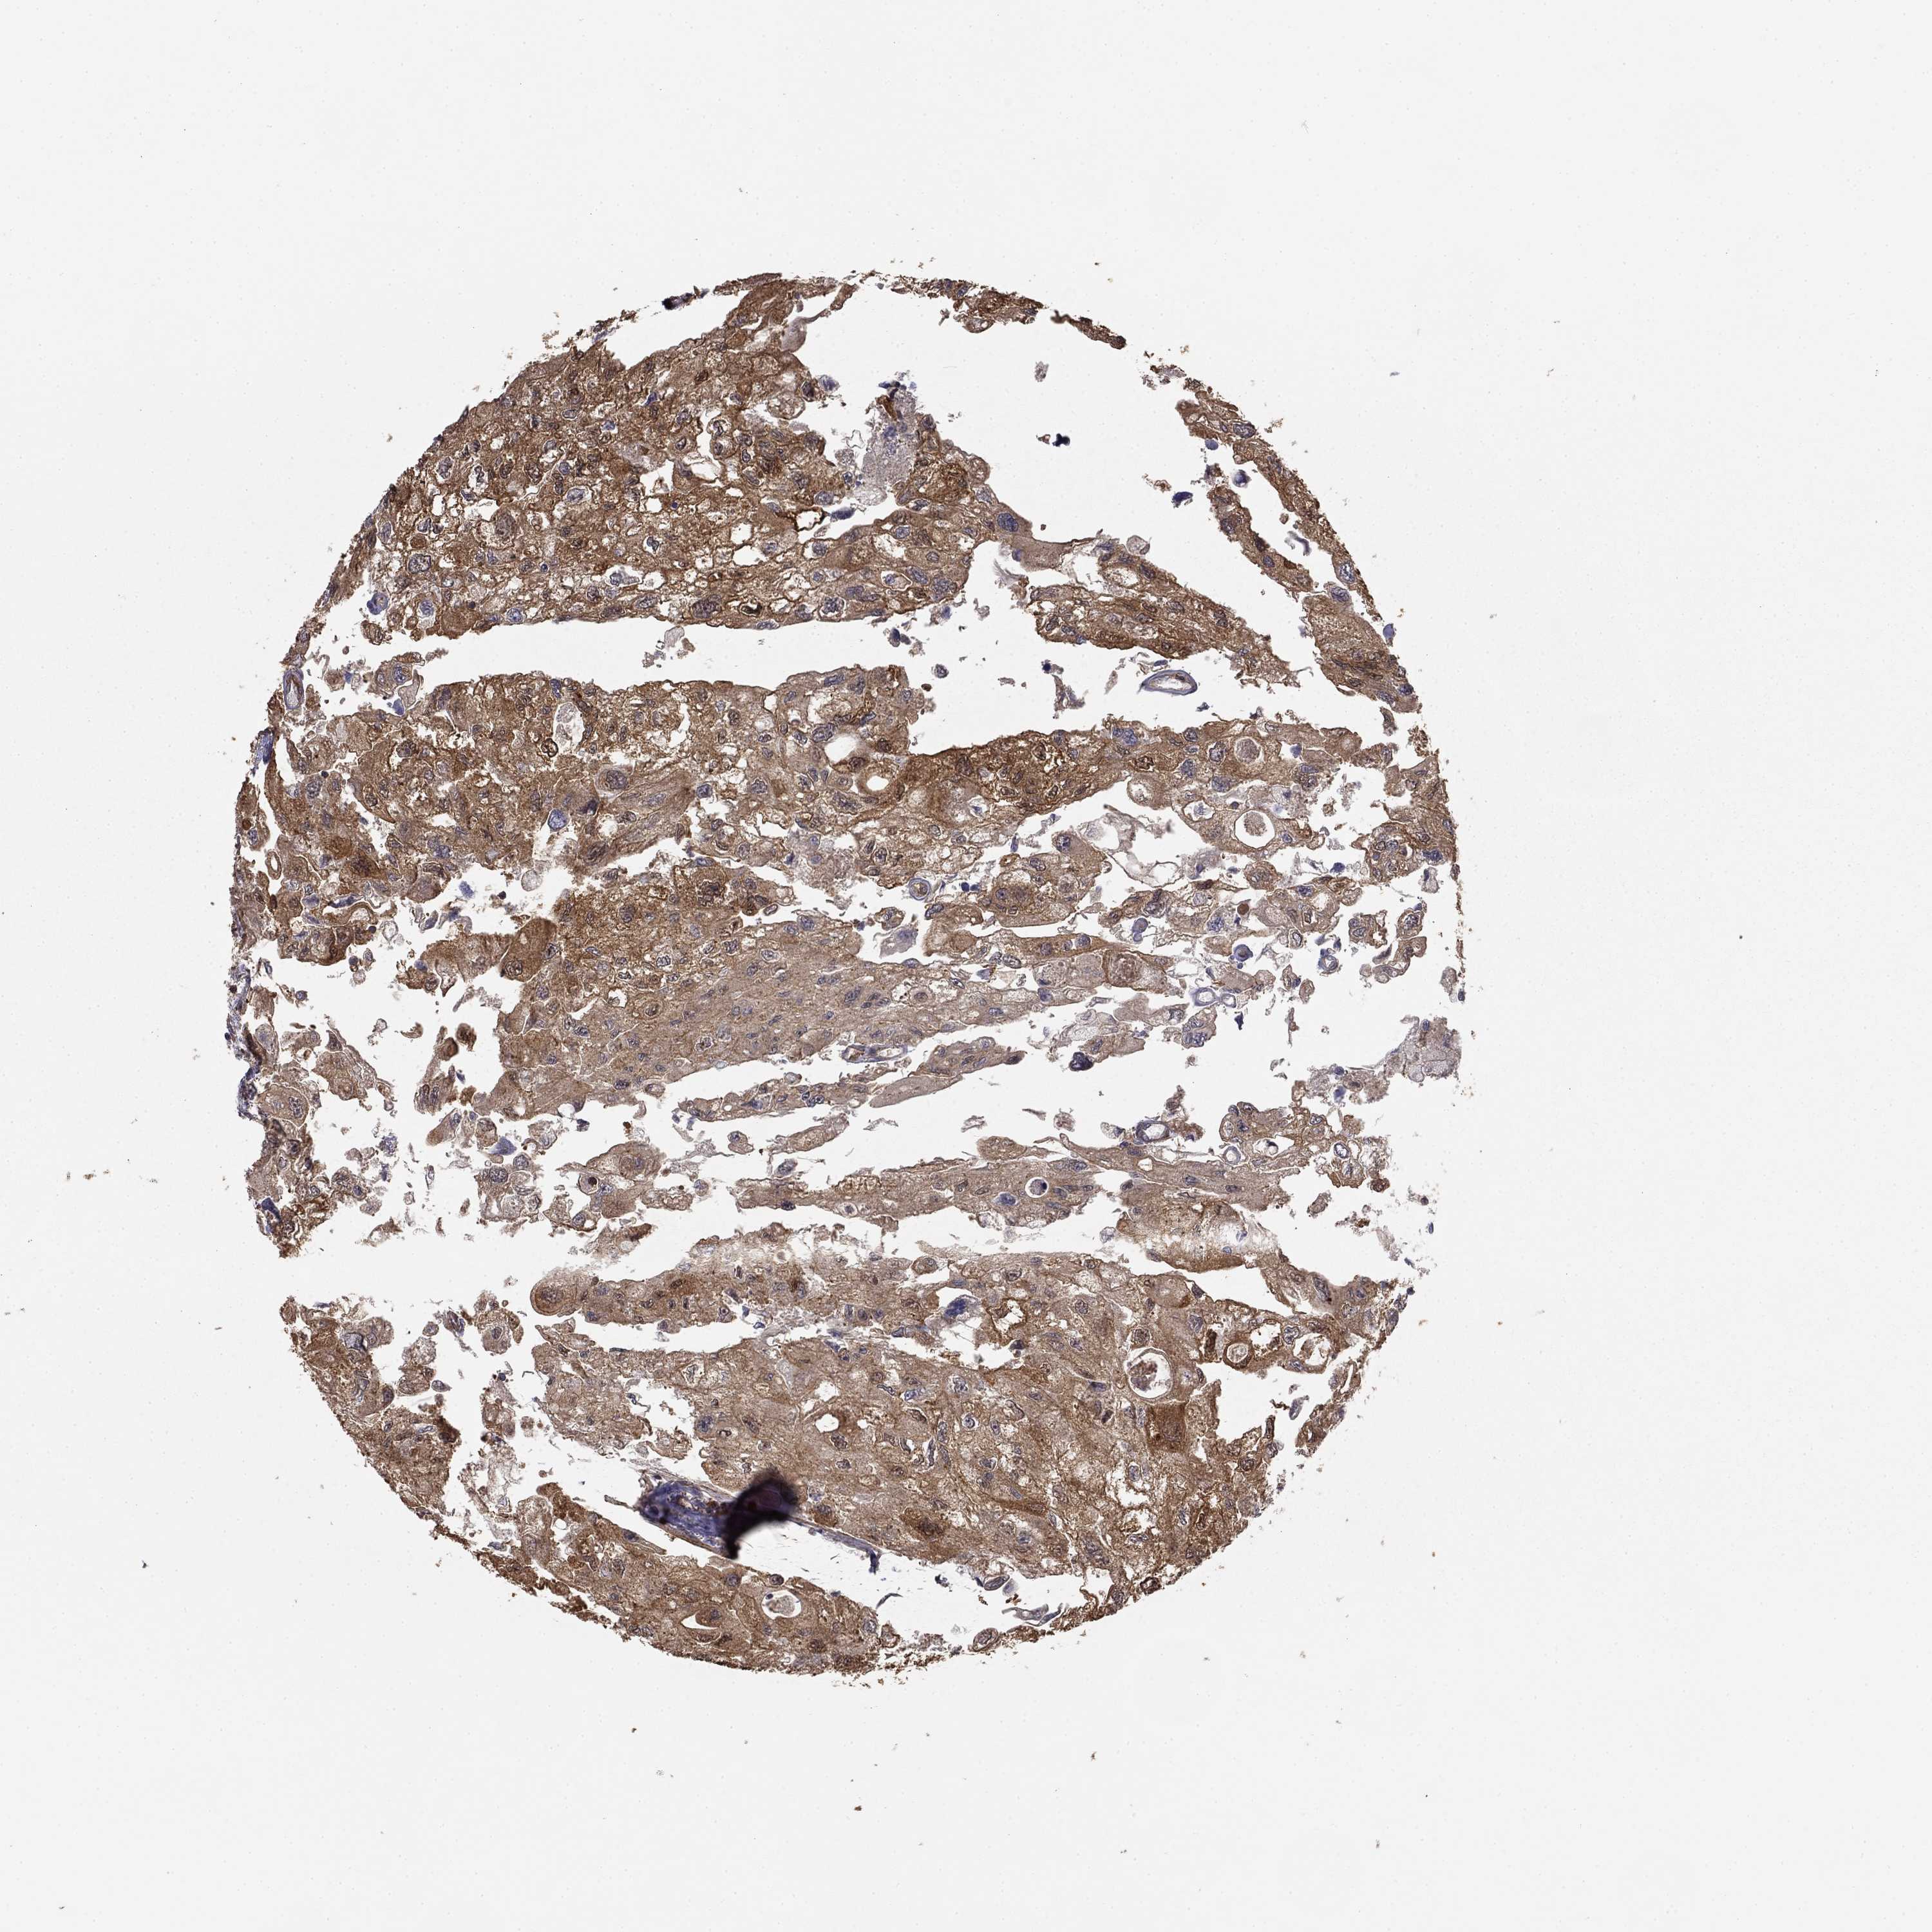

UROTHELIAL CANCER - Protein expressioni

A mouse-over function shows sample information and annotation data. Click on an image to view it in a full screen mode. Samples can be filtered based on level of antibody staining by selecting one or several of the following categories: high, medium, low and not detected. The assay and annotation is described here.

Note that samples used for immunohistochemistry by the Human Protein Atlas do not correspond to samples in the TCGA dataset.

Antibody stainingi

Antibody staining in the annotated cell types in the current human tissue is reported as not detected, low, medium, or high, based on conventional immunohistochemistry profiling in selected tissues. This score is based on the combination of the staining intensity and fraction of stained cells.

Each image is clickable and will lead to virtual microscopy that enables deeper exploration of all samples and also displays staining intensity scores, fraction scores and subcellular localization as well as patient and tissue information for each sample.

Antibody HPA055969

Antibody HPA062366

Staining

High

Medium

Low

Not detected

Intensity

Strong

Moderate

Weak

Negative

Quantity

>75%

75%-25%

<25%

None

Location

Nuclear

Cytoplasmic/membranous

Cytoplasmic/membranous,nuclear

Urothelial carcinoma, High grade

Urothelial carcinoma, NOS

Urothelial carcinoma, Low grade